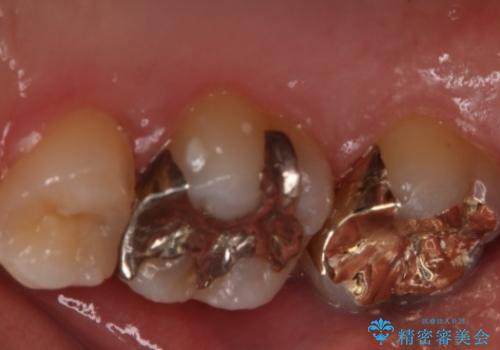

ゴールドは歯科治療に適している金属と言われ、アレルギー反応も起こしません。

奥歯の治療によく使われます。

- 右上6番の銀歯のやりかえを希望し来院された患者様です。

切削量や形状からインレーでの治療を計画しました。

ご本人が金歯を希望されたため、ゴールドインレーでの治療を選択しました。